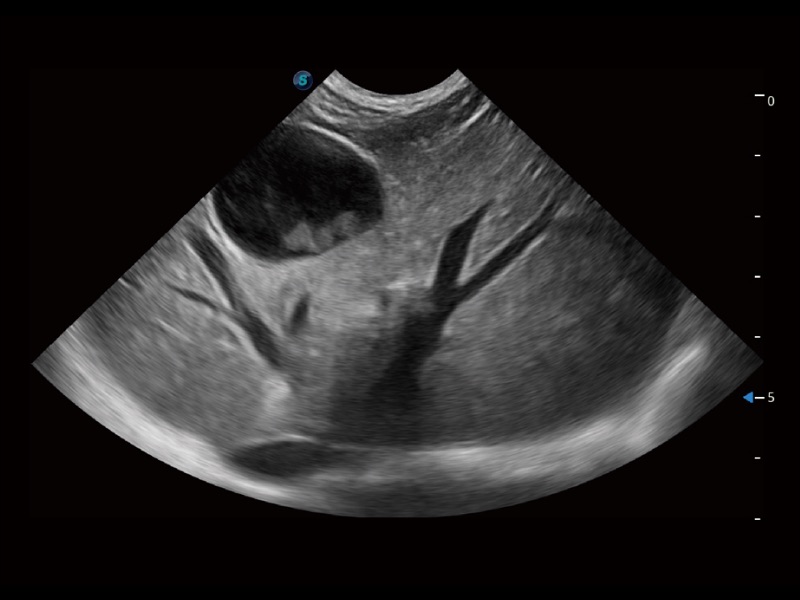

(犬)四腔心

(犬)胎儿主动脉弓立体血流